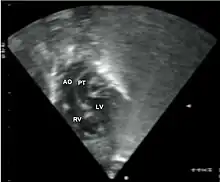

Abbreviations: LV and RV=left and right ventricle, PT=pulmonary trunk, VSD=ventricular septal defect, PS=pulmonary stenosis.

Abbreviations: RA=right atrium, RV=right ventricle, LV=left ventricle, PT=pulmonary trunk, LPA and RPA=left and right pulmonary artery.